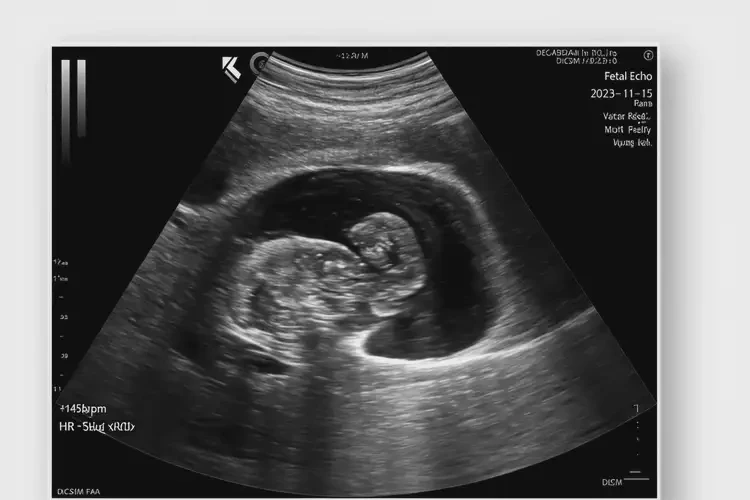

孕2周1天胎心率87還要保胎嗎(圖1)